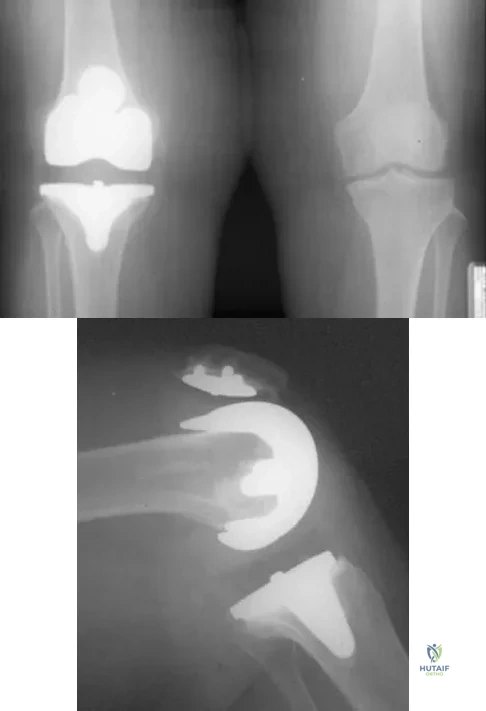

A 63-year-old woman reports giving way of the knee and pain after undergoing primary total knee arthroplasty (TKA) 1 year ago. Examination reveals that the knee is stable in full extension but has gross anteroposterior instability at 90 degrees of flexion. The patient can fully extend her knee with normal quadriceps strength. Studies for infection are negative. AP and lateral radiographs are shown in Figures 12a and 12b, respectively. What is the appropriate management?

Explanation